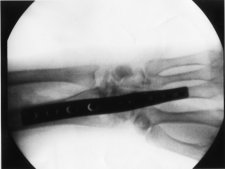

X-Ray with Plate 2 Days after Plate Removal 1 Day Later

Bledsoe Brace Xray with Plate

4 Weeks Post-Op Plate and Screws